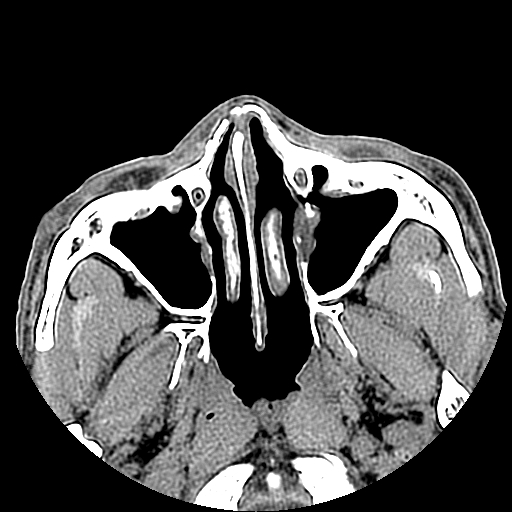

以下是引用liaoqiang在2008-7-16 21:15:00的发言:[br]右侧鼻骨骨折

以下是引用zxd95在2008-7-16 21:39:00的发言:[br]右侧上颌骨额突骨折。[br][br][br][br]